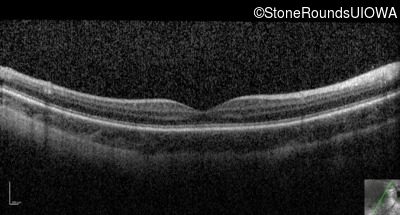

Optical Coherence Tomography - Right - 10/200 sc

Exemplar / OCT Stack

OCT Stack